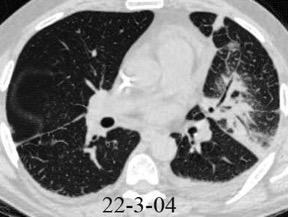

< 80% hallazgos pulmonares. Colección con calcificaciones. Micronódulos en intersticio subpleural y broncovascular con engrosamiento septal. Respuesta paradójica frecuente.

Ocasionalmente nivel hidro-aéreo por fístula broncopleural Consolidación........3% Ganglios……….....39%

Derrame...................65-98.5%

Lesiones pleurales. ........38 %

Afect. cisura interlobar….9%

Pl. mediastínica........... 1.5%

Afect. pulmonar 26/66 … 39%

Cambios fibróticos..........17%

Cavitación ......................12%

Nódulos heterogéneos.....6%